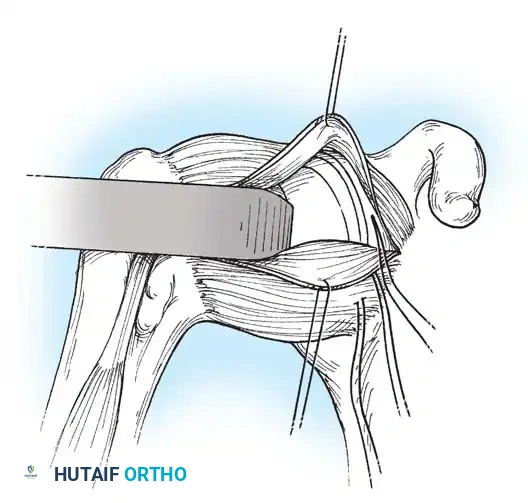

Subscapularis Management

Exposure of the anterior capsule requires navigating the subscapularis muscle. Historically, a vertical tenotomy was performed; however, modern techniques favor a subscapularis split or a peel to preserve the integrity of the muscle belly and its tendinous insertion.

- The Split: A horizontal split is made in the subscapularis at the junction of its middle and inferior thirds, extending from the lesser tuberosity medially.

- Separation: The subscapularis is carefully elevated off the underlying anterior joint capsule. This plane can be scarred in revision cases, requiring meticulous sharp dissection to avoid inadvertent capsulotomy.

Capsulotomy and Joint Inspection

A vertical or T-shaped capsulotomy is performed based on the degree of capsular laxity and the planned shift.

- For a standard Bankart repair with an inferior capsular shift, a vertical incision is made 1 cm medial to the humeral articular margin. A horizontal limb can be added to create superior and inferior capsular flaps.

- Tagging sutures are placed in the capsular flaps for traction.

- A Fukuda retractor is placed within the joint to retract the humeral head laterally and posteriorly, exposing the anterior glenoid rim and labrum.